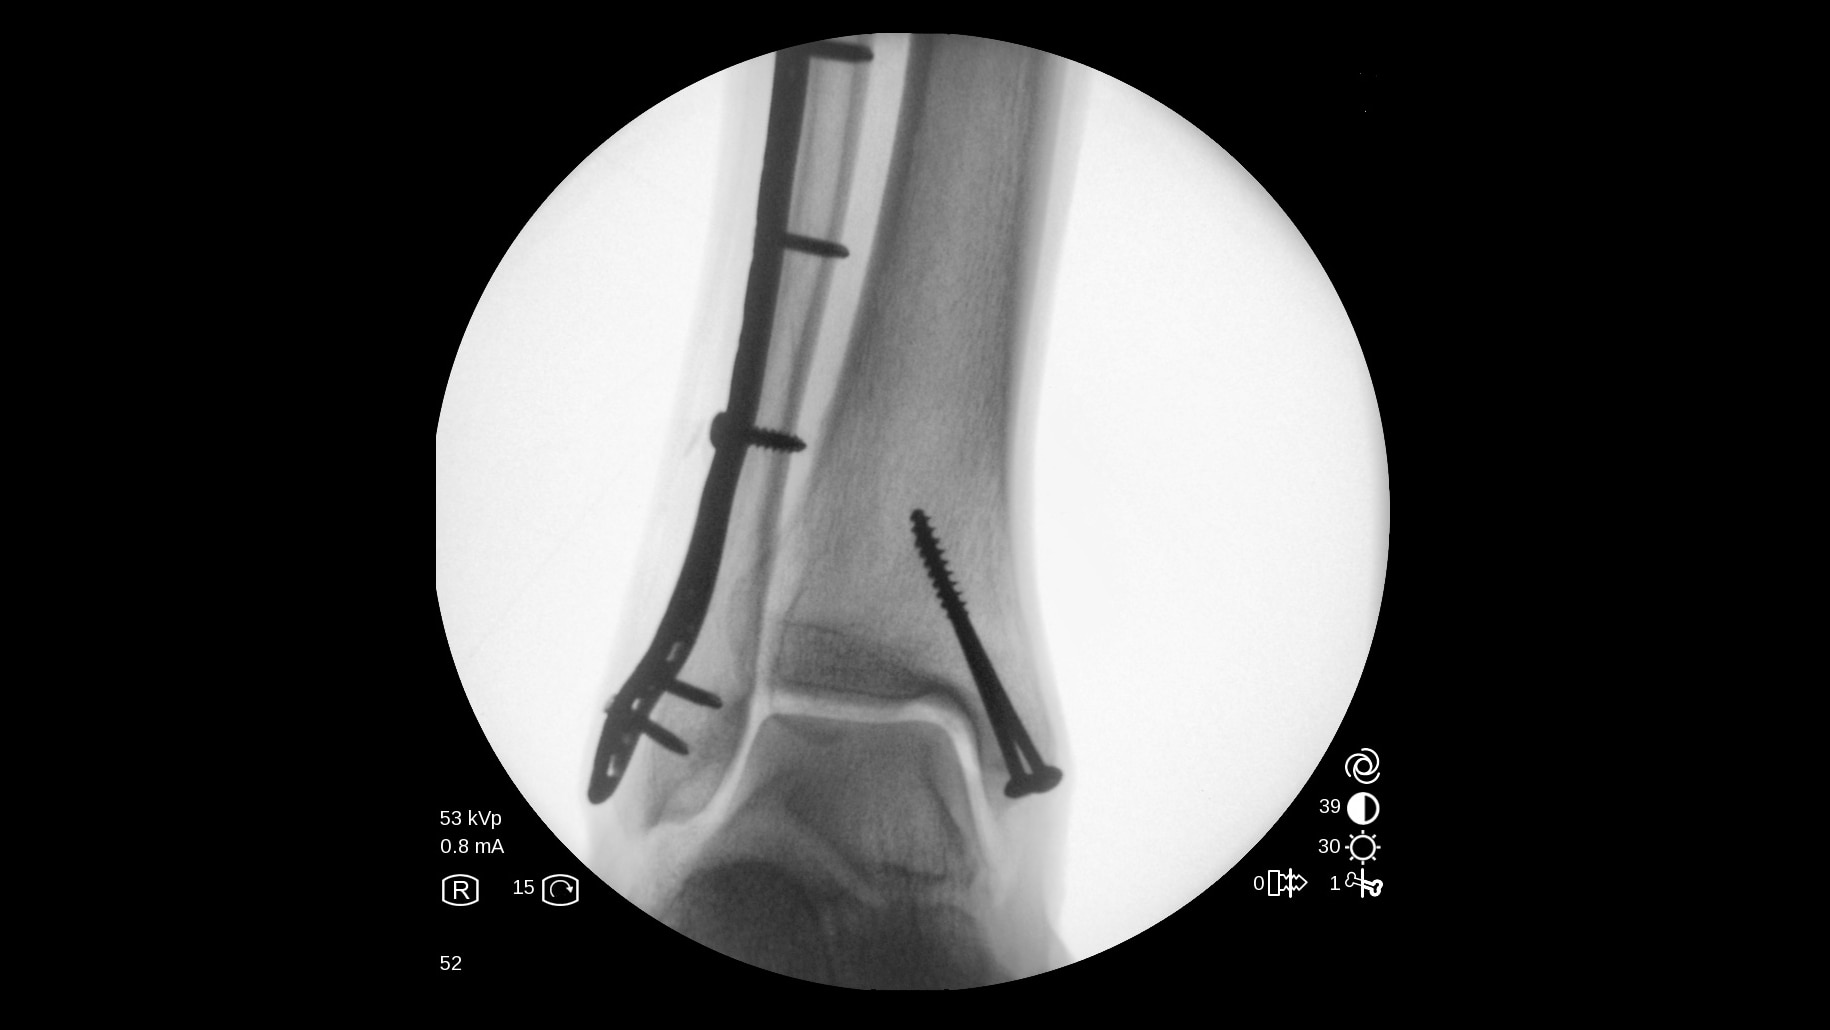

The OEC One all-in-one mobile C-arm offers superb imaging capabilities, made more accessible for a variety of procedures — from pain management to peripheral vascular. Enjoy image processing advancements in clear, detailed images.

Get the images you need without adjusting system settings from the first shot to the last shot with OEC image processing software.

OEC One utilizes automatic intelligence software to sense anatomy and provide high quality imaging at optimal mA and kV levels, even when anatomy is not properly centered in the field of view.